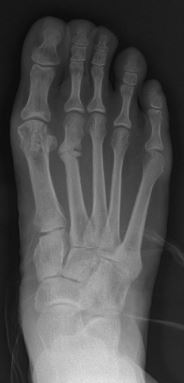

Primus varus deformity is the leaning of the first metatarsal bone away from the second metatarsal and towards the opposite foot (Fig. 1). As it leans over, its head sticks out to form the bunion bump and it also widens the forefoot to cause shoes feeling too tight. Thus when bunion pain becomes unmanageable, surgical correction is to narrow the forefoot by repositioning of the first metatarsal head back to its normal position. This can be done by osteotomy (bone-breaking), soft tissue (non-osteotomy) or fusion techniques.[citation needed]

Syndesmosis procedure addresses specifically the two fundamental problems of metatarsus primus varus deformity that gives rise to the bunion deformity. They are leaning and instability of the first metatarsal bone . Syndesmosis procedure uprights the leaning first metatarsal bone with strong binding sutures between it and the second metatarsal bone (Fig. 2) and then also stabilizes it uniquely by creating a fibrous connecting bridge between these two bones (Fig. 3, 4). First metatarsal bone can be readily realigned because by definition of the metatarsus primus varus deformity its first metatarsal is abnormally loose and mobile.[citation needed]

The surgical technique of syndesmosis procedure originated from the osteodesis procedure that was first described by Botteri in 1961.[6] It has since been studied and reported by Pagella in 1971,[7] Irwin in 1999[8] and Wu in 2007.[2] Syndesmosis itself is a normal anatomical structure for the purpose of connecting two parallel long bones side by side, such as the tibia and fibula bones. The naming of syndesmosis procedure was thus to reflect the essence of the technique which is to create a “syndesmosis” mechanism to provide permanent stability to the first metatarsal to prevent recurrence. Both the bone-binding-sutures and syndesmosis-connection concepts are unique and revolutionary in a world of bunion surgery overwhelmingly dominated by osteotomy (bone-breaking) tradition.[citation needed]